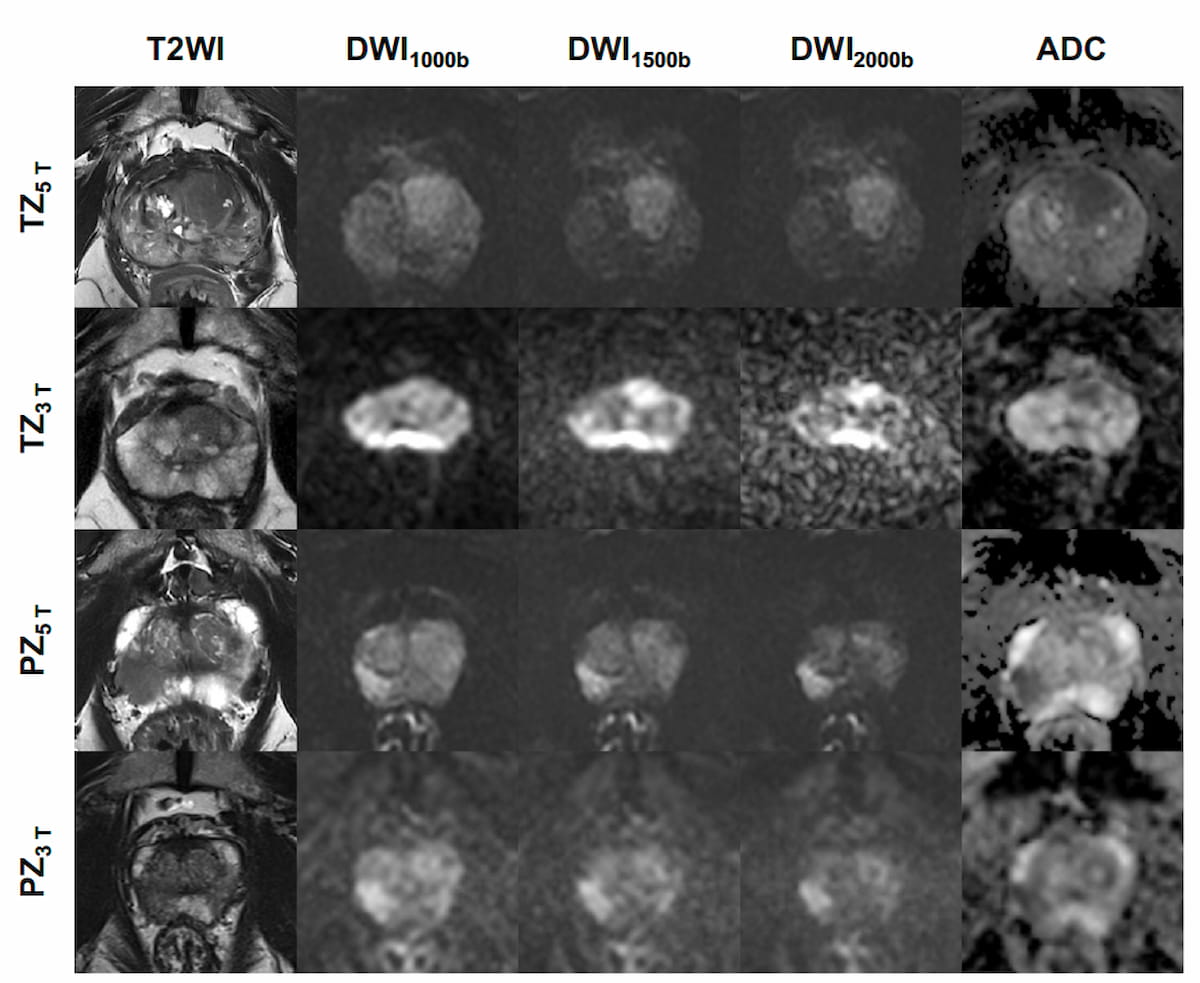

The study authors noted a greater than 47 percent higher overall image quality score for 5T MRI in contrast to 3T MRI (74.6 percent vs. 26.9 percent). The researchers also found that excellent or good delineation was achieved for T2-weighted imaging (T2WI) in 83.6 percent of cases and diffusion-weighted imaging (DWI) in 82.3 percent of cases for 5T MRI in comparison to 28.4 percent and 55.2 percent, respectively, for 3T MRI.

“ … The image quality at 5T was significantly improved for both T2WI and DWI sequences. These results alleviate the major concern that a higher field strength might increase artifacts,” pointed out Xiong and colleagues.